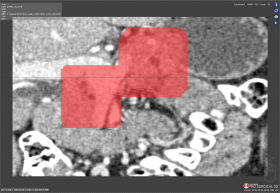

Compare Ground truth segmentations against Test segmentations using the Intersection Over Union (IOU), Overlap, and Bleed from the Algorithm Scoring Tool to evaluate the accuracy of your Test segmentations.

How the Algorithm Scoring Tool Works